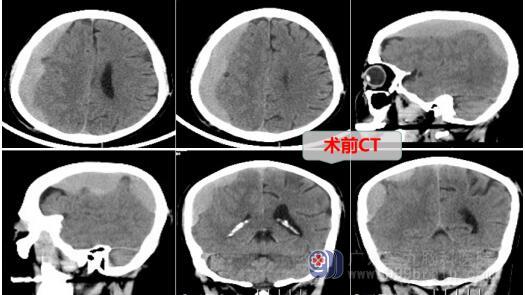

医生接诊时发现郭爷爷呈嗜睡状,立即安排入院并完善各项检查,CT显示新发右侧额颞顶部硬膜下亚急性期-慢性期血肿,脑组织受压。医疗团队经过详细评估,认为右侧额颞顶硬膜下血肿明确,患者已出现嗜睡症状,口服药物治疗效果不佳。立即急诊为郭爷爷进行了血肿切开外引流术。